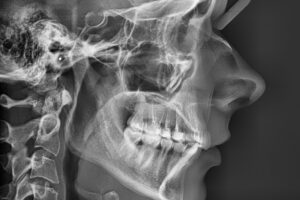

| Radiografia digitală retroalveolară | Radiografia cefalometrică – teleradiografia |

| Radiografia digitală panoramică (opt) | Tomografia Computerizată CBCT – CT 3D |